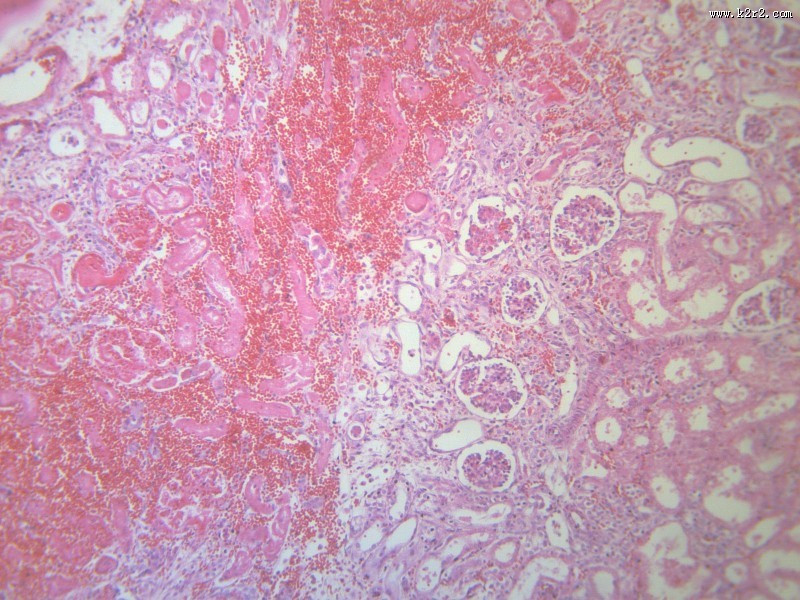

肾小管坏死 - 第10张

第 10 / 12 张

肾小管坏死

图集中 / 共有 12 张图片

肾凝固性坏死

肾小管水肿

医学

显微切片